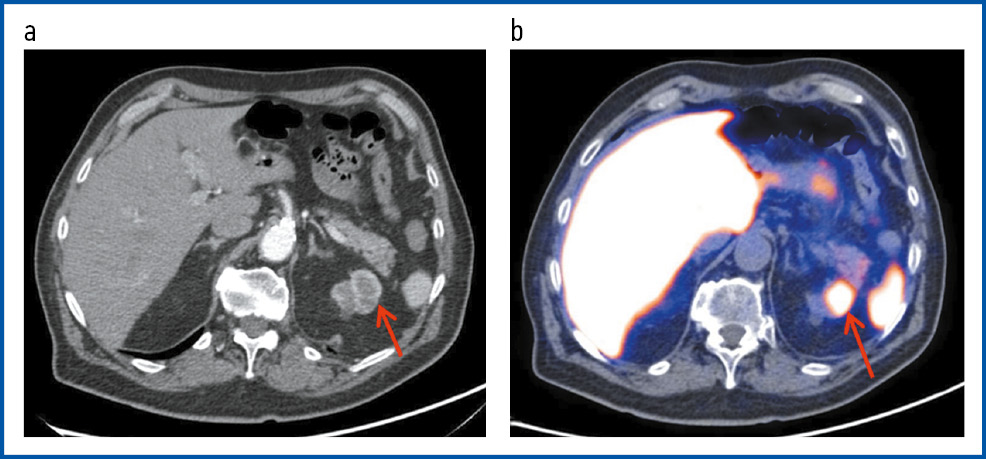

Рис. 4. Пациент А., 72 года. ПЭТ/КТ с 18F-PSMA. РПЖ, стадия pT3bN1M0G2. 3 + 4 = 7 по Глисону. Состояние после радикальной простатэктомии с тазовой лимфаденэктомией. Первично-множественный метахронный светлоклеточный ПКР. Латентный период – 26 мес. На MIP (a), аксиальной проекции КТ (b) и ПЭТ/КТ-исследовании (c) – состояние после радикальной простатэктомии. В области цистуретрального анастомоза справа визуализируется узловое образование с гиперфиксацией РФП, SUVmax 12,36 – рецидив.

Fig. 4. Patient A., 72 years old. PET/CT with 18F-PSMA PCa, pT3bN1M0G2 stage. Gleason score 3 + 4 = 7. State after radical prostatectomy with pelvic lymphadenectomy. Primary multiple metachronous clear cell RCC. The latency period was 26 months. On MIP, the axial view of CT, and pet/CT imaging, the state after radical prostatectomy was visualized. In the area of bladder-urethral anastomosis, a nodule with RPA hyper uptake was visualized on the right, SUVmax 12.36. Findings consistent with relapse.